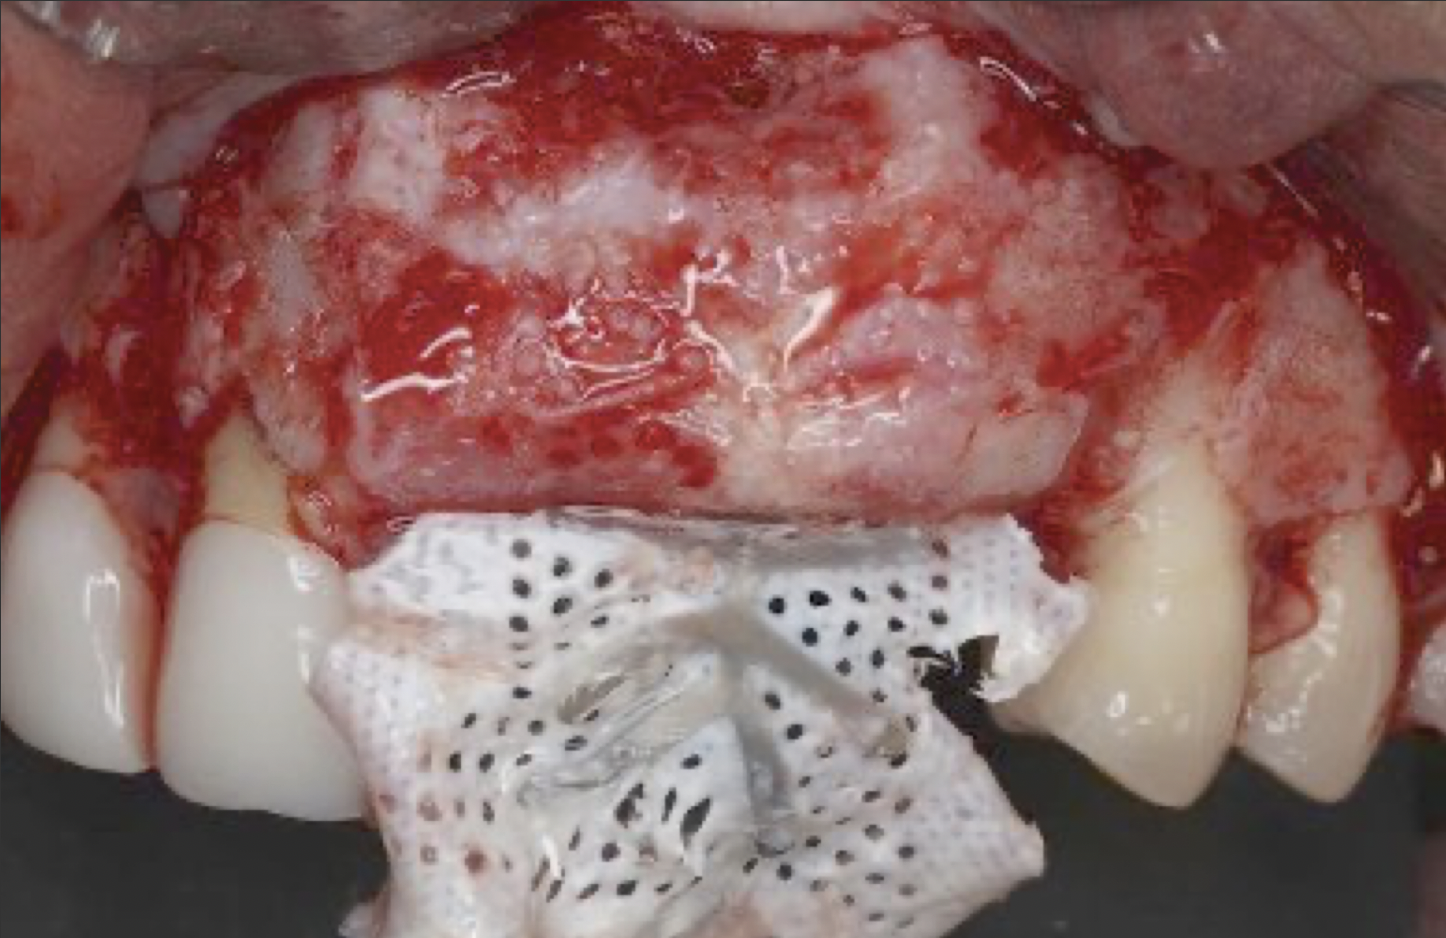

This approach was effective in increasing the horizontal and vertical soft-tissue thickness around the three implants. Nevertheless, a distortion of the MGJ was still present (Figure 13). Therefore, 3 months after the iCTG augmentation, it was decided to perform a second soft-tissue augmentation procedure with the goal of repositioning the MGJ in an adequate level on the buccal aspect, increasing the width of the keratinized mucosa at the implant sites. A modified apically positioned flap was performed (Figure 14). Two labial strip gingival grafts were harvested from the anterior mandible and maxilla and sutured onto the recipient bed with a 7-0 polyglycolic acid resorbable suture.5,17,18 The residual periostium was covered with a non-crosslinked xenogeneic collagen matrix (Figure 15).

Fig 11. Soft-tissue augmentation with two CTGs.

Figure 11

Fig 12. Two additional CTGs were placed between the implants (ie, the “iceberg” CTG approach).

Figure 12